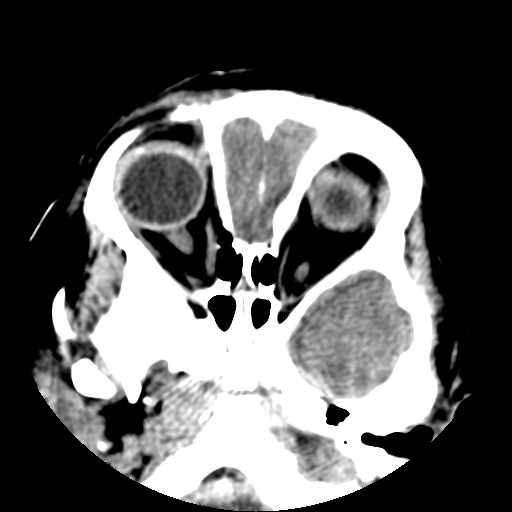

以下是引用深泽交通医院在2009-10-16 8:25:00的发言:[br]右眼环出血伴异物

以下是引用卜一在2009-10-16 15:01:00的发言:[br]右眼球挫裂伤伴异物!

以下是引用拾荒者在2009-10-17 18:38:00的发言:[br]鼻面部皮下积气,右侧睑缘及眼球壁高密度异物影,左侧眼球壁晶状体内侧缘处是圆形低密度影。低密度异物?应提请眼科医生注意。